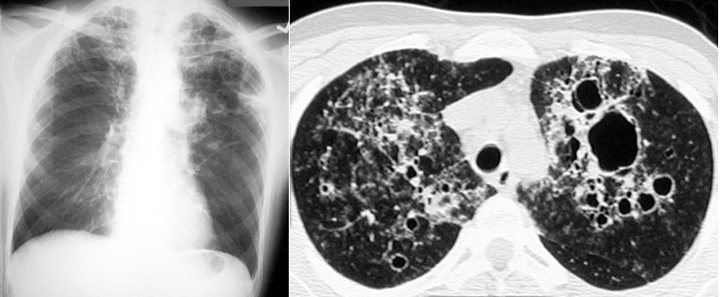

Рентгеновские снимки при пневмоцистной пневмонии